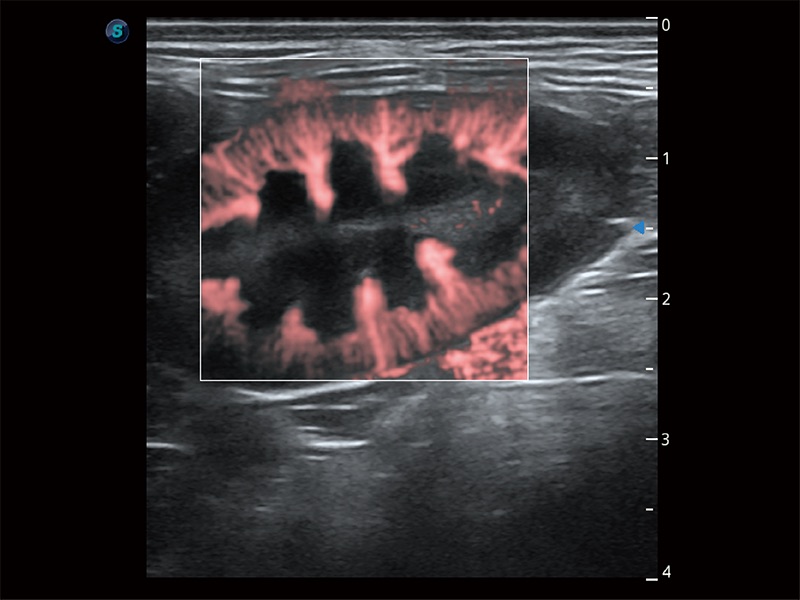

• Bright Flow 立体血流成像

在传统二维血流成像的基础上,呈现血流的立体感,具有动感的生命力之美。即便是微小的血管也能轻松应对,提高了血流的视觉敏感性。

(犬)胎儿主动脉弓立体血流